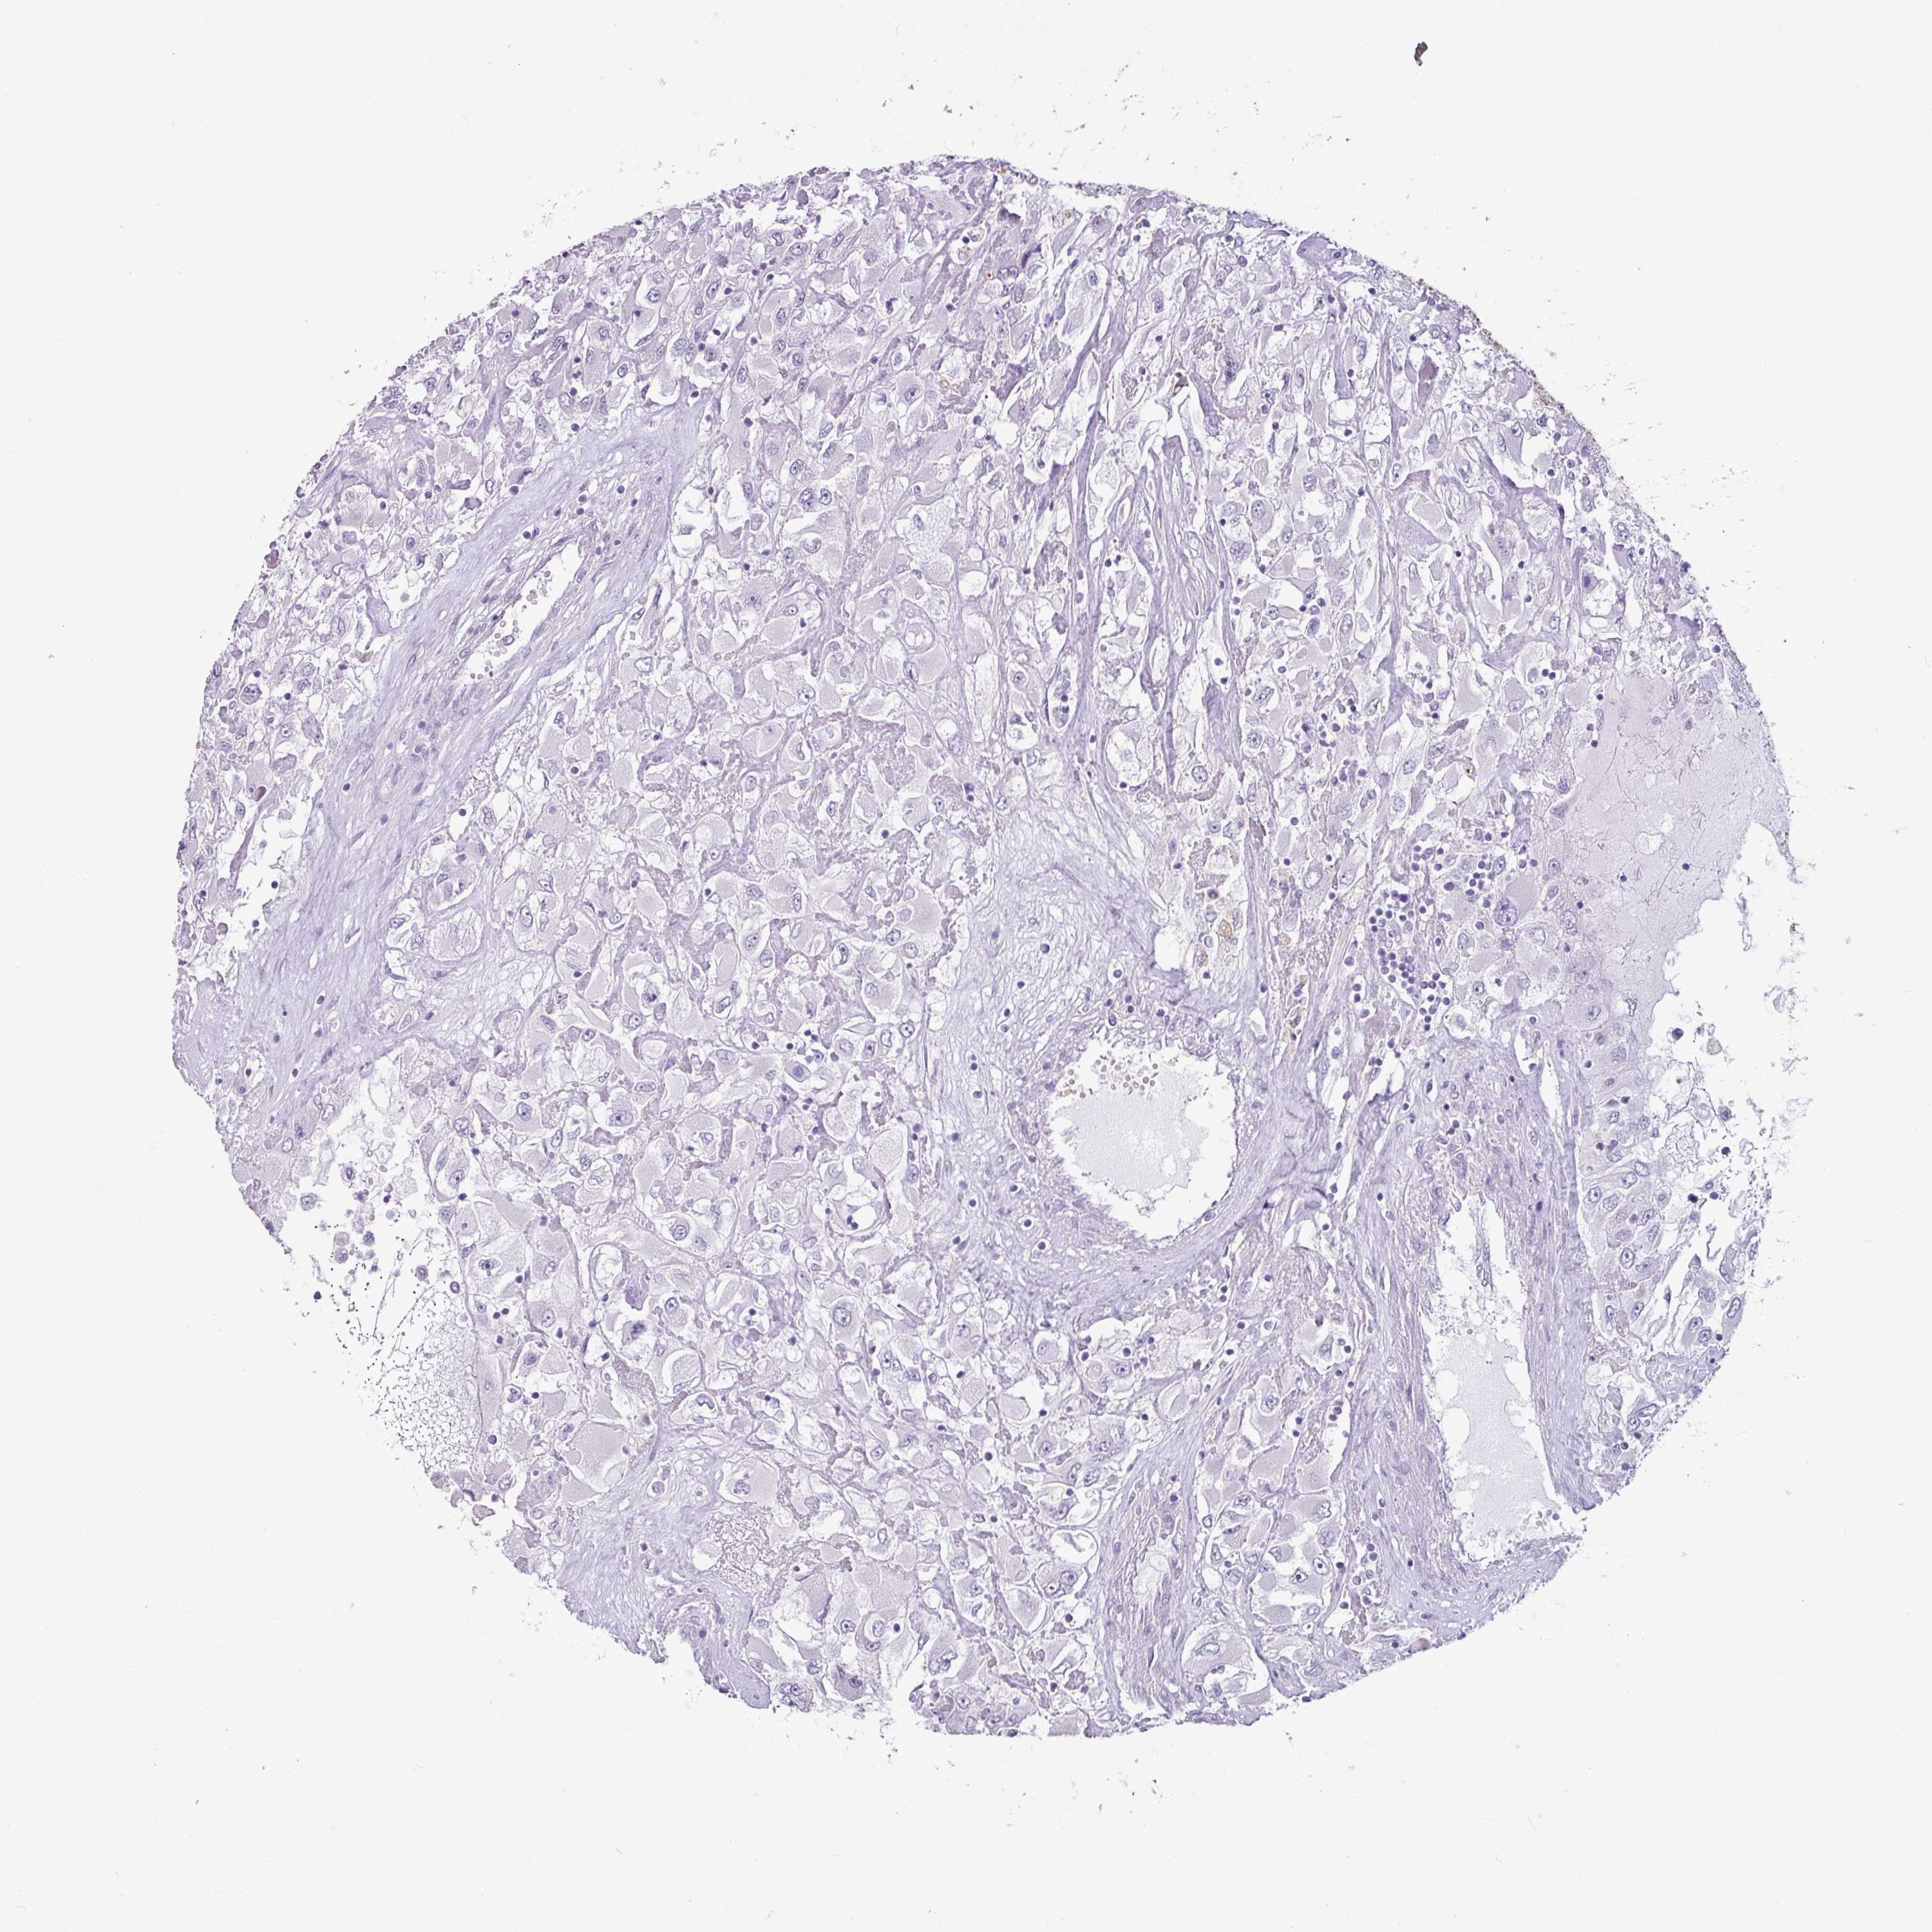

CANCER RENAL CANCER Show tissue menu

KICH TCGA KIRC TCGA KIRC VALIDATION KIRP TCGA PROTEIN RCC CPTAC PROTEIN EXPRESSION